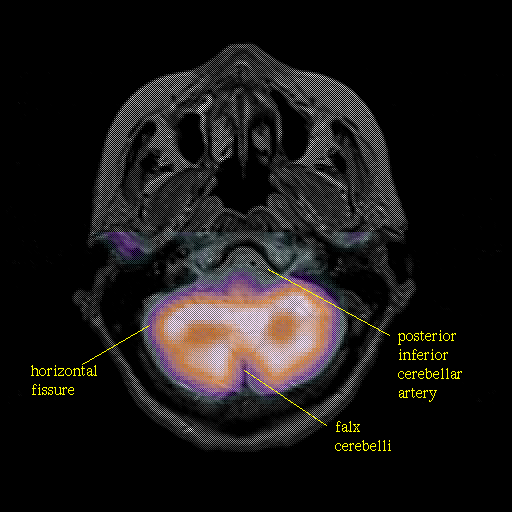

Pointers

Labeled